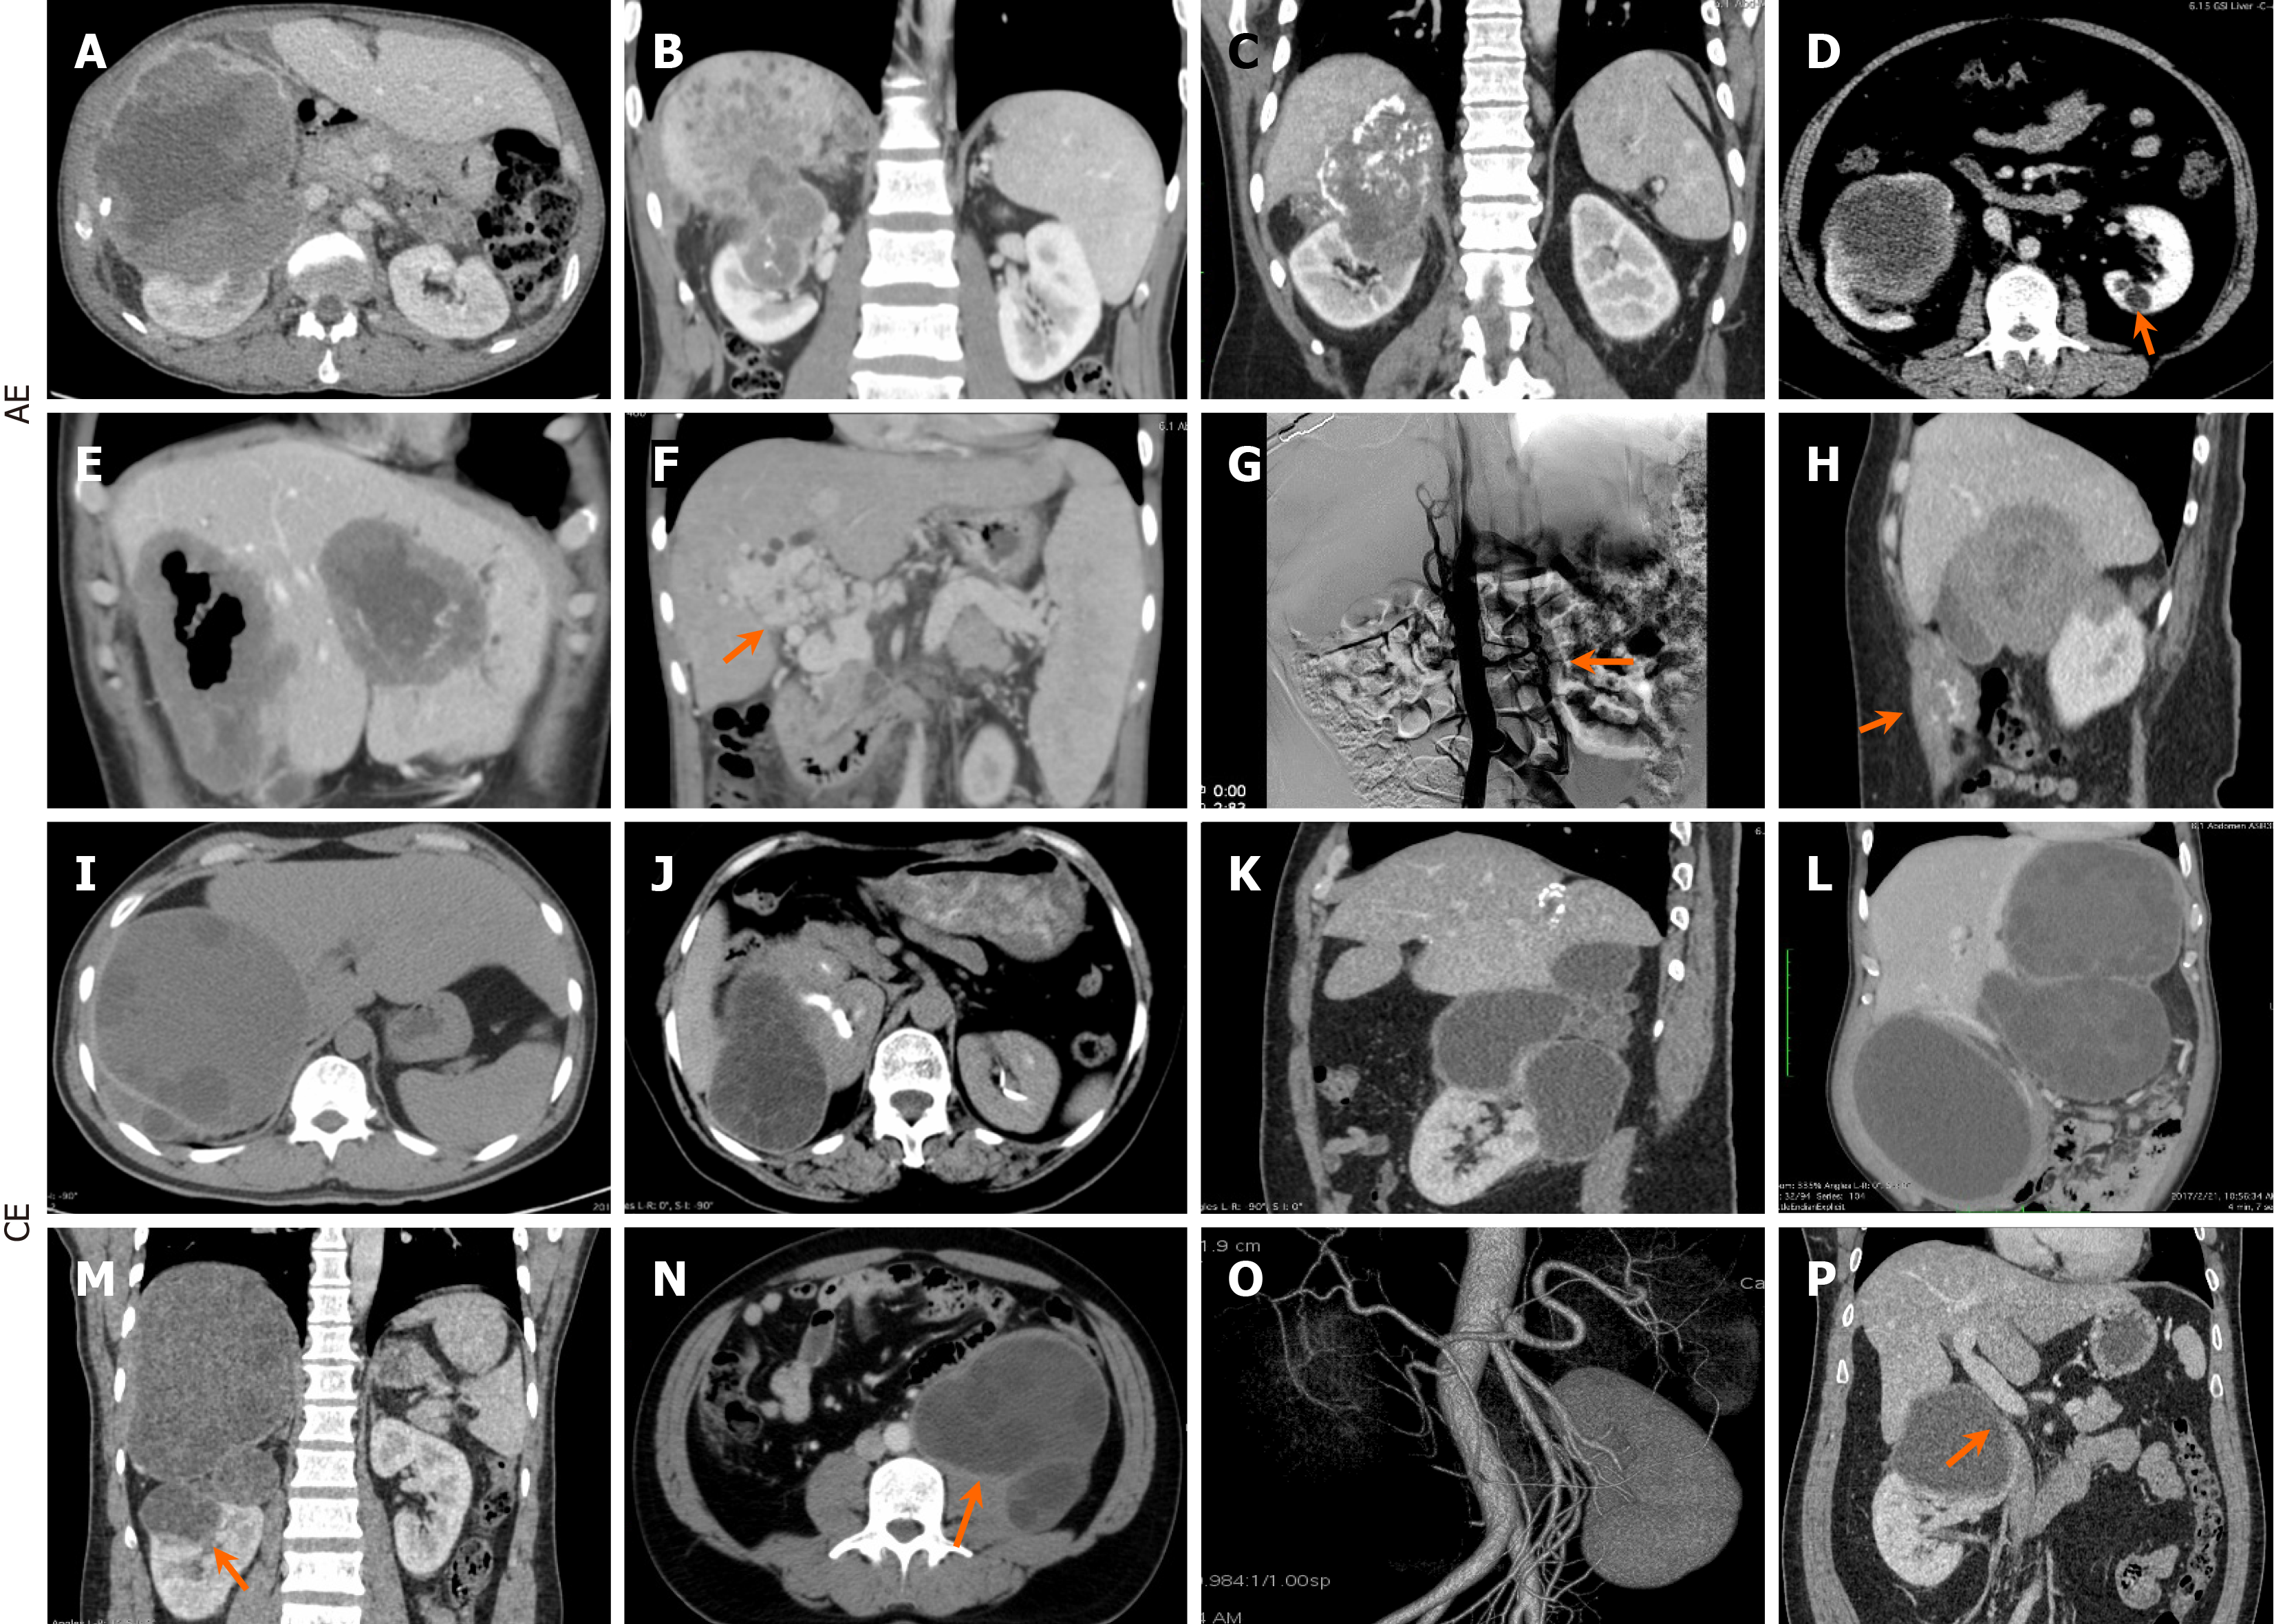

Figure 2 Radiological findings.

A-C: Right-sided hepatorenal alveolar echinococcosis (AE) lesion involvement was prevalent in AE cases; D and E: Isolated single lesions were observed in the left kidney (D) and the left lateral lobe of the liver (E); F-H: AE comorbidities included portal vein cavernous transformation (F), bilateral collateral circulation (G) secondary to severe inferior vena cava (IVC) involvement, and abdominal wall invasion (H); I-M: In contrast, cystic echinococcosis (CE) presented with solitary and multiple large cysts bilaterally; N-P: CE comorbidities included psoas muscle invasion (N), renal function impairment (O), and IVC involvement (P). AE: Alveolar echinococcosis; CE: Cystic echinococcosis.